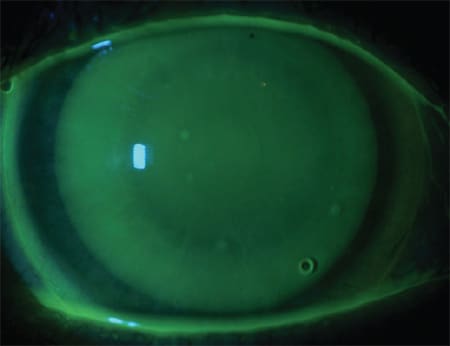

The lenses aligned with the cornea, cleared the limbus, and landed on the sclera evenly. The patient reported that she could barely feel the lenses and gave them a 9-out-of-10 comfort rating. Upon dispensing, the lenses fit well (Figures 9 and 10) and provided excellent vision. She has now been wearing this contact lens design for two years with less than 0.50D change in refraction.

Figures 9 and 10. Case 4 optic section of the lenses showing alignment over the central cornea.